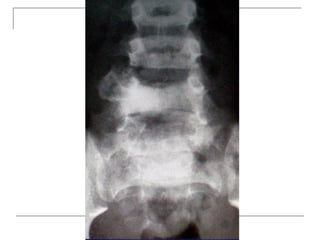

Plain radiograph

   AP

-loss of lumbar lordosis

-reduced disc space

-osteophytes

-deformity

-fracture (increase interpedicular distance)

-osteoporosis

-pedicle disruption

Plain radiograph  AP -loss of lumbar lordosis -reduced disc space -osteophytes -deformity -fracture (increase interpedicular distance) -osteoporosis -pedicle disruption

• 25.

Lateral -fracture/wedging -kyphosis -spondylolisthesis  Oblique -spondylolysis (SCOTTIE DOG)